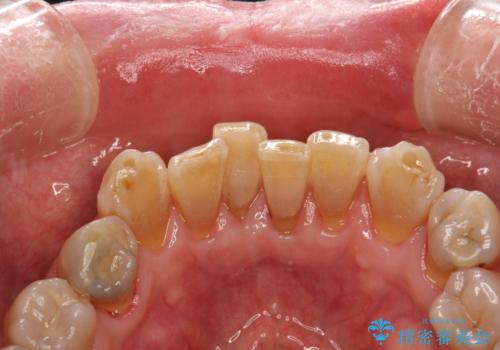

歯周外科前のクリーニング

- 歯周外科を行う前に、しっかりと汚れを除去し外科治療がスムーズに行えるようにとのことでPMTC30分コースを行いました。

治療前のクリーニングを行うことで、より処置がスムーズに行えること・処置後の腫れや感染予防にもなります。また、外科治療をおこなった後は、傷口の治りを待つため、しっかりとブラッシングできない状態になります。そのため処置前に、なるべくお口の中を清潔にしておくことが大切です。

親知らずの抜歯やインプラント治療の前などに、PMTC(専門器具による歯の機械的な清掃)を行うことをおすすめします。